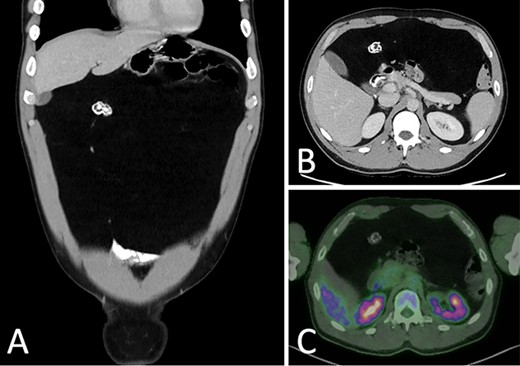

Abdominal ultrasound (US) revealed a well-demarcated, mildly hyperechogenic mass lesion apparently occupying the left lobe of the liver and measuring 6 × 25 × 24 cm. Both contrast-enhanced computed tomography (CT) and magnetic resonance imaging (MRI) demonstrated a well-circumscribed lipomatous mass within the greater omentum, measuring 9 × 24 × 27 cm, without discrete enhancing soft tissue components or local invasive features (Fig. 1). There were several foci of internal coarse calcification on CT corresponding with areas of low T1 and T2 signals and thin peripheral rim enhancement on MRI suggestive of focal fat necrosis. Intra-abdominal mass effect was evident but without acute complications. No metabolically active disease was demonstrated on fluorodeoxyglucose positron emission tomography (FDG-PET) (Fig. 2).

(A) CT portal venous phase axial slice demonstrating a well-circumscribed lipomatous lesion within the greater omentum measuring 9 × 26 × 24 cm; (B) MRI T2-weighted axial slice demonstrating intermediate T2 signal of the lesion.